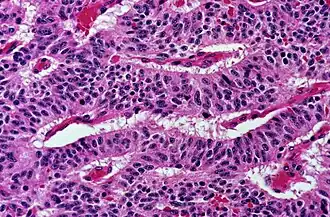

The most commonly used stain in histology is a combination of hematoxylin and eosin (often abbreviated H&E). Hematoxylin is used to stain nuclei blue, while eosin stains the cytoplasm and the extracellular connective tissue matrix of most cells pink. There are hundreds of various other techniques which have been used to selectively stain cells. Other compounds used to color tissue sections include safranin, Oil Red O, congo red, silver salts and artificial dyes. Histochemistry refers to the science of using chemical reactions between laboratory chemicals and components within tissue. A commonly performed histochemical technique is the Perls' Prussian blue reaction, used to demonstrate iron deposits in diseases like Hemochromatosis.[2]

The histological slides are examined under a microscope by a pathologist, a medically qualified specialist who has completed a recognised training program. This medical diagnosis is formulated as a pathology report describing the histological findings and the opinion of the pathologist. In the case of cancer, this represents the tissue diagnosis required for most treatment protocols. In the removal of cancer, the pathologist will indicate whether the surgical margin is cleared, or is involved (residual cancer is left behind). This is done using either the bread loafing or CCPDMA method of processing. Microscopic visual artifacts can potentially cause misdiagnosis of samples. Scanning of slides allows for various methods of digital pathology, including the application of artificial intelligence for interpretation.

Following are examples of general features of suspicious findings that can be appreciated from low to high magnification on histopathology:

Architectural pattern of any suspicious cells, in this case nests of cells, as well as components of the intervening stroma. -

Cellular arrangement, including crowding and cell polarity (common tendencies among cells at the border, such as elongation or "palisading" in this case). Amount of mitoses can also be appreciated at this level. -